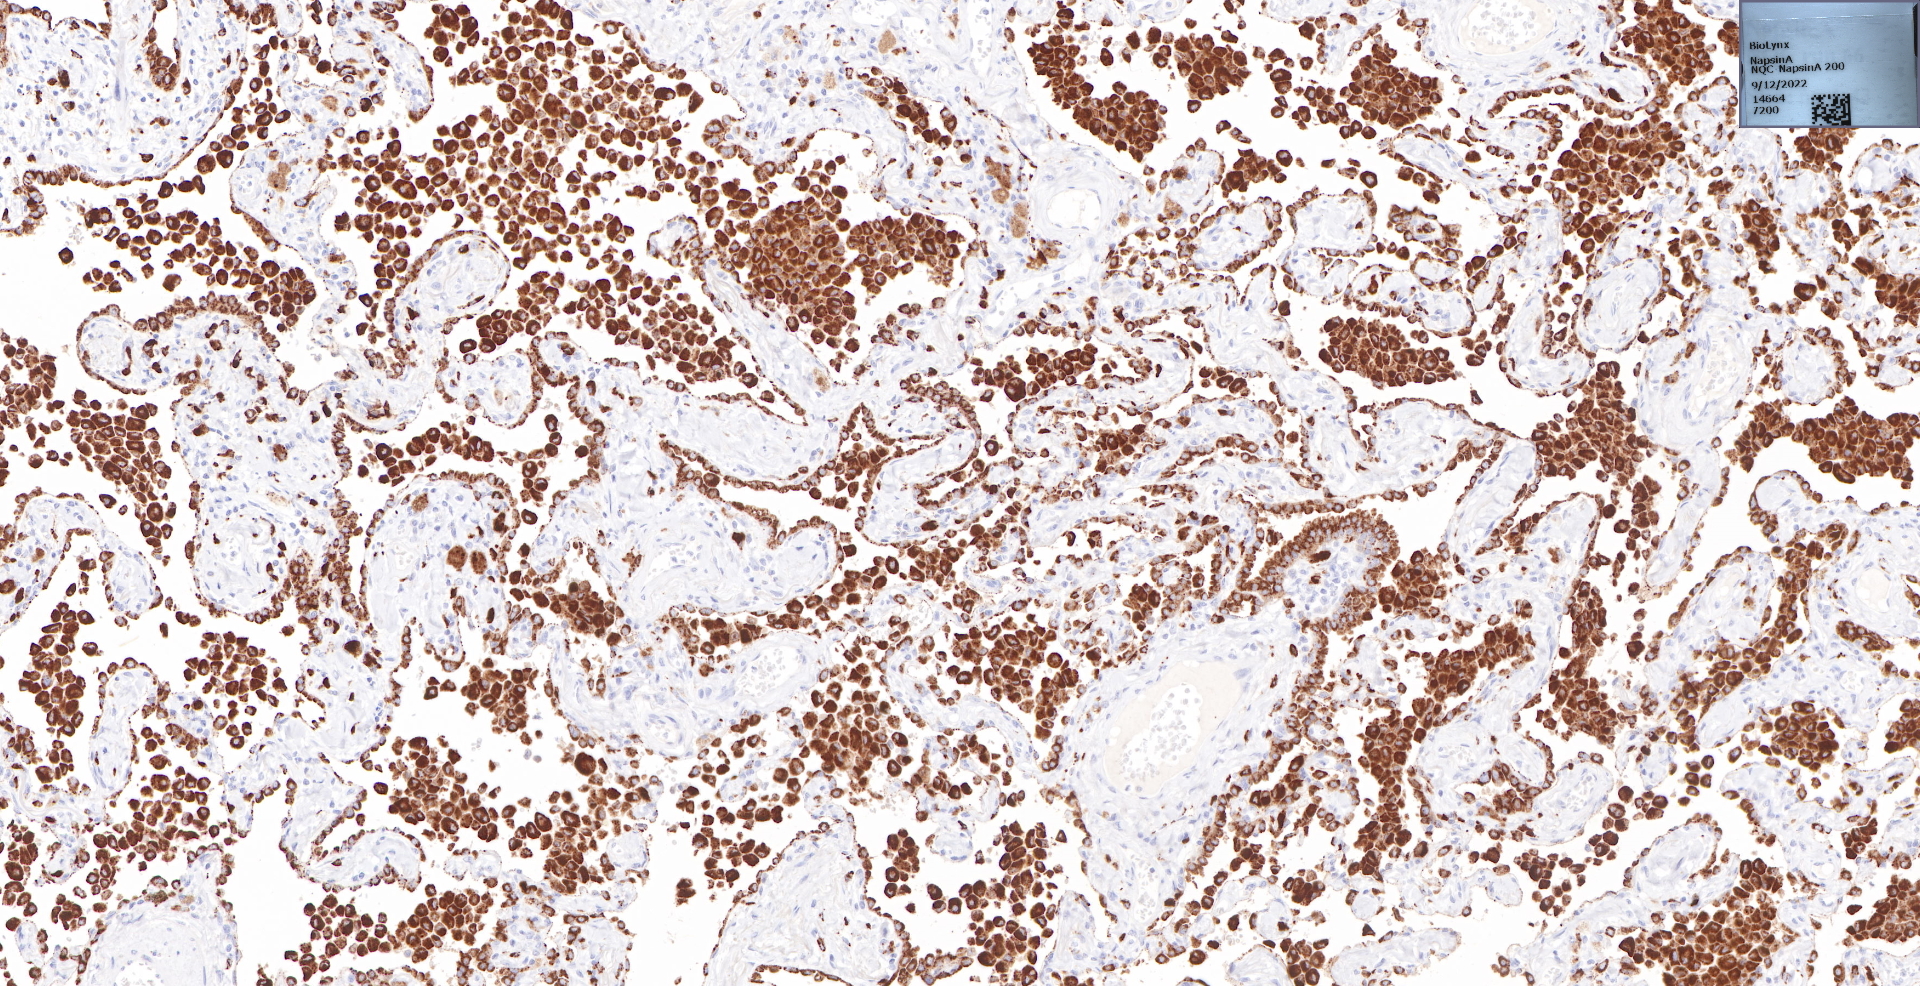

Napsin A

undefined

BP6083 Napsin A 肺染色

肺腺癌.jpg

BP6083 Napsin A 肺腺癌染色